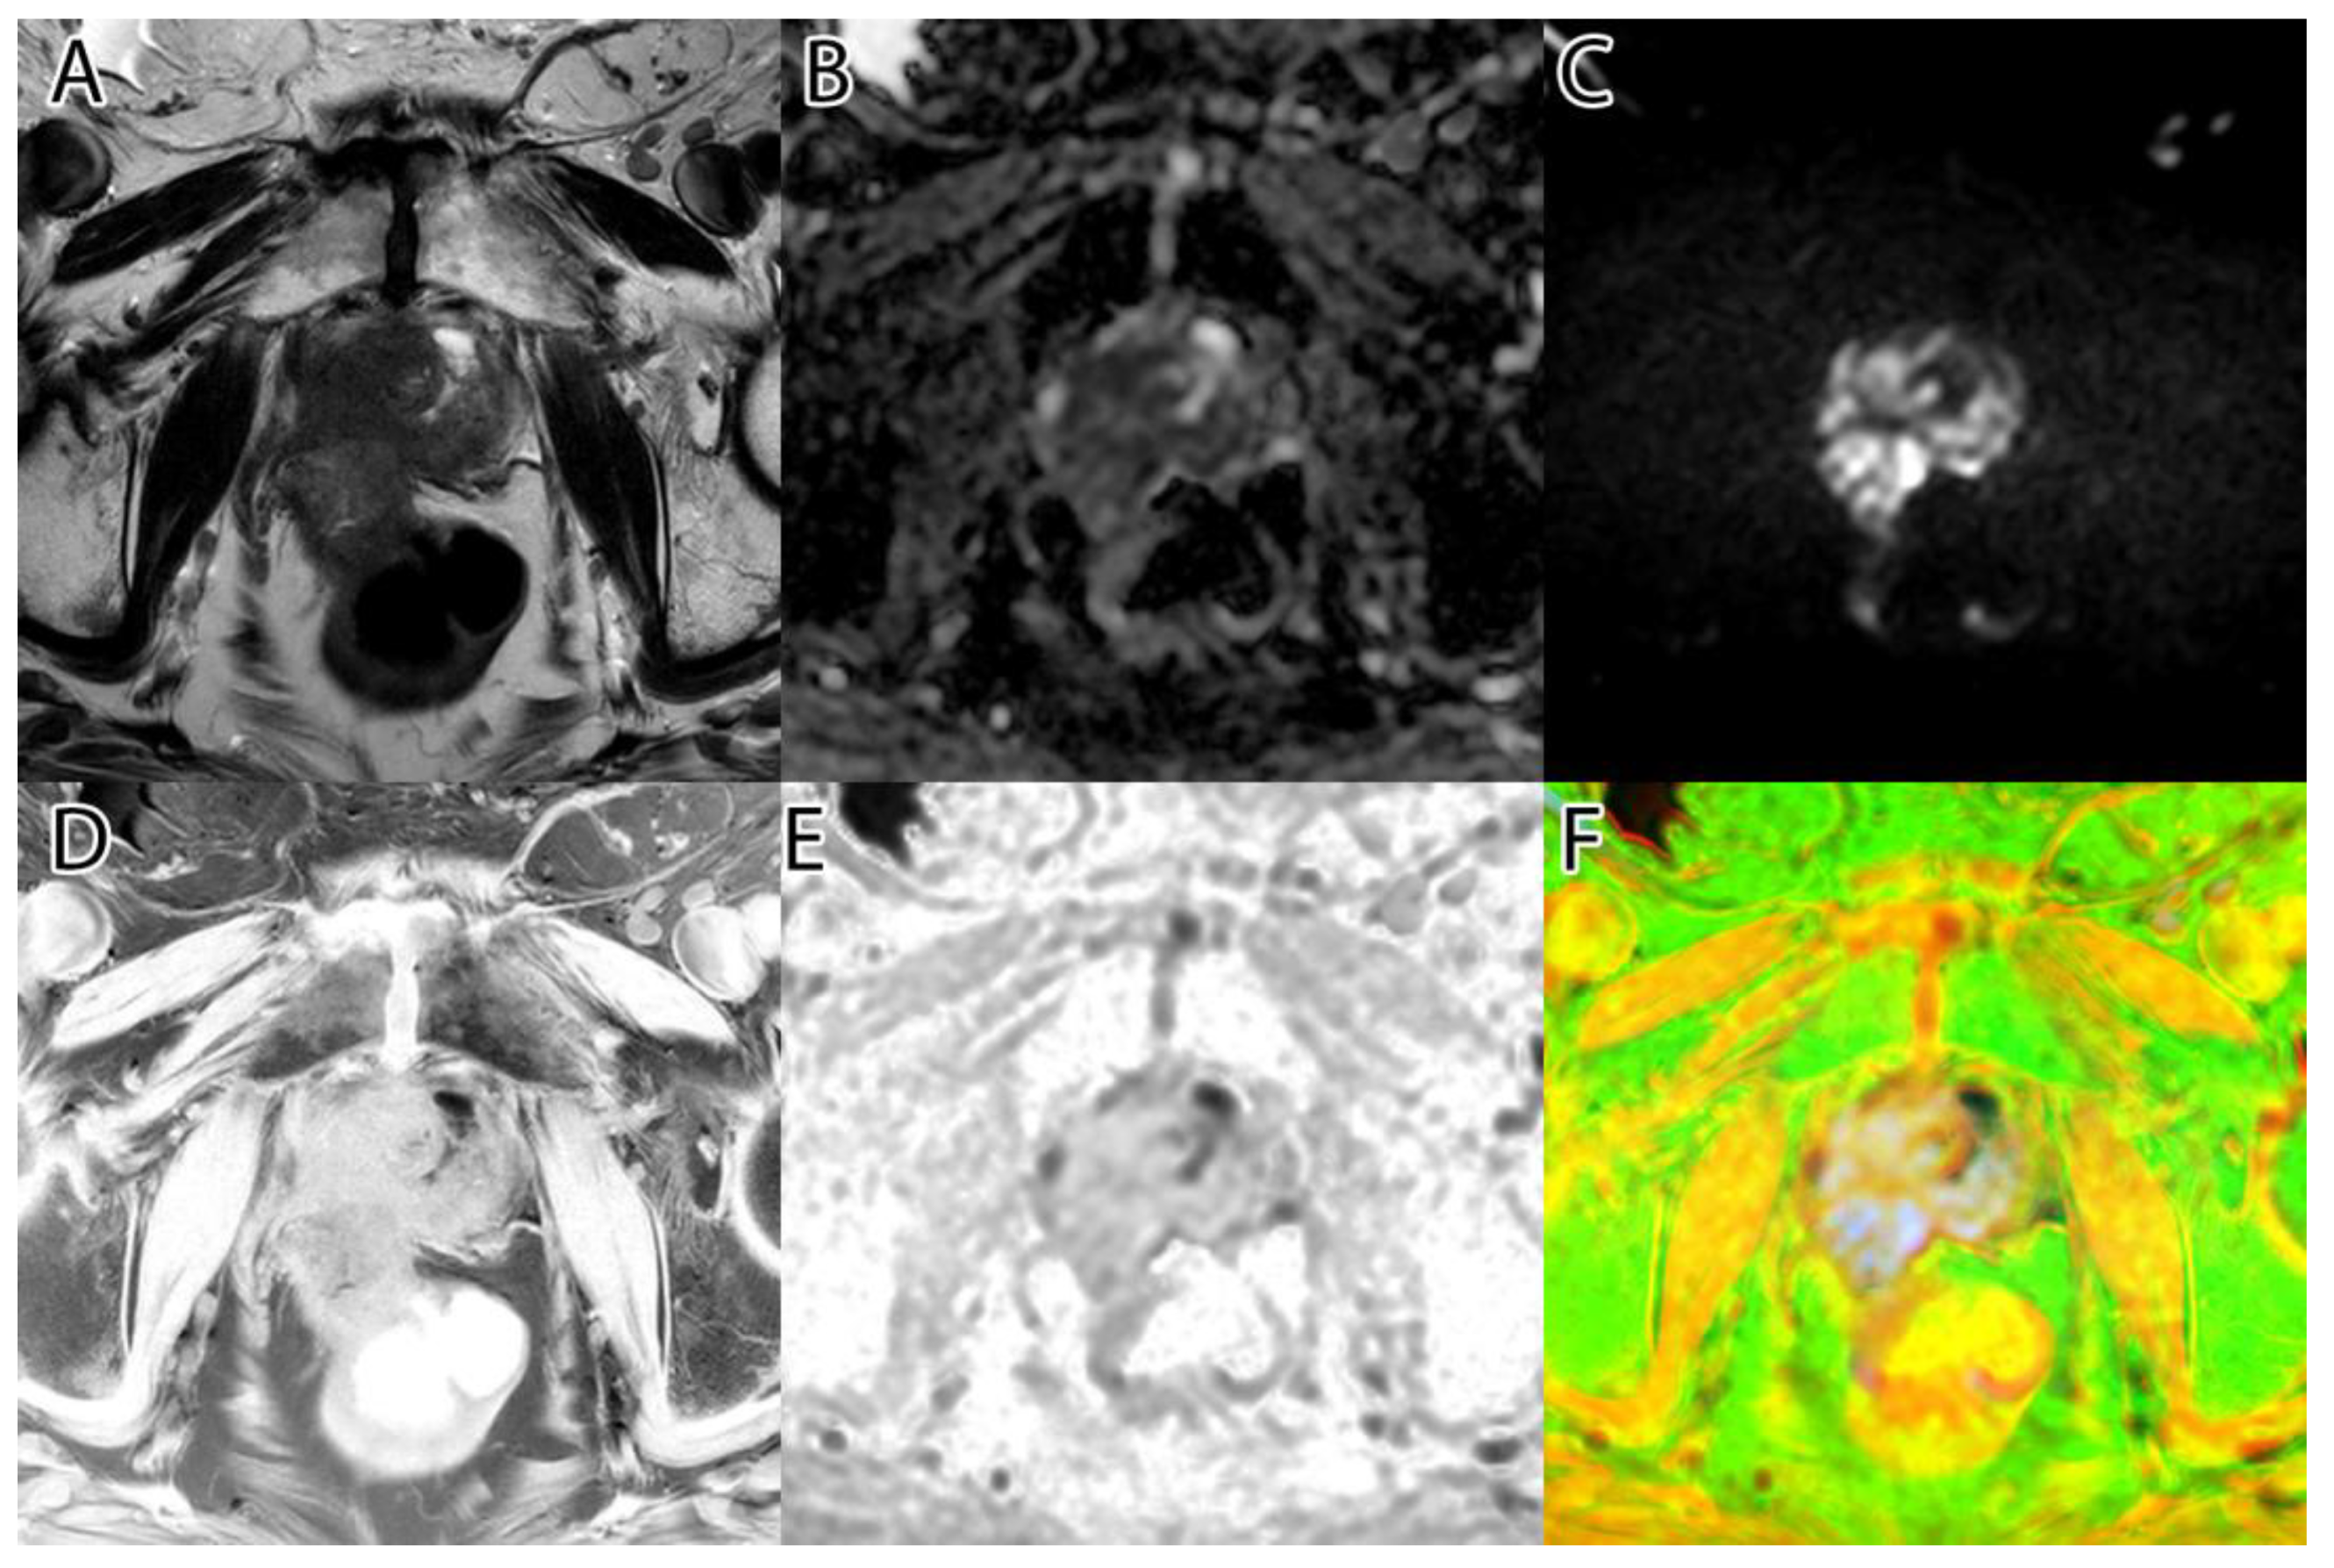

Figure 3. PI-RADS 5 patient: (A)—T2WI; (B)—ADC; (C)—DWI; (D)—RGB fused image; (E)—grayscale tumor intensity image; (F)—‘jet’-mapped tumor intensity image.

Samples of the computed tumor intensity images can be seen in Figure 2 for a PI-RADS 2 patient and in Figure 3 for a PI-RADS 5 patient. Notice the difference in “jet” intensity between the control patient and the patient with extraprostatic invasion.

Figure 9. An incidental finding in a patient with extrapelvic pathology, so the field of view is large, and the protocol is not ideal. However, our algorithm proved accurate because the hypersignal area in DWI is not PCa: (A)—T2WI; (B)—ADC; (C)—DWI; (D)—T2 and DWI fused image; (E)— our ‘jet’-mapped tumor intensity image.